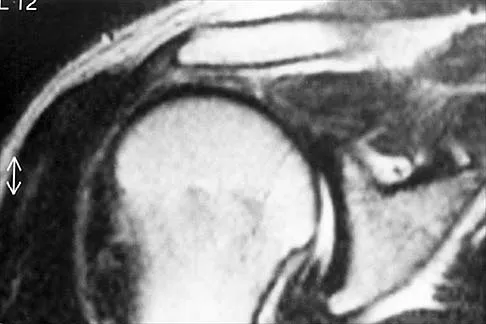

Question 23

A coronal MRI scan through the shoulder joint is shown in Figure 26. The cyst indicated by the arrow will most likely cause compression of what nerve?

Explanation